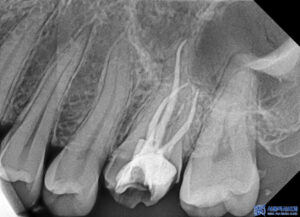

파노라마를 촬영하여 확인해 보니,

뿌리 쪽에 염증이 있는 것을

볼 수 있었는데요.

겉으로 보이는 크라운에는

특별한 문제가 없어 보였지만,

방사선 사진상 치아 뿌리 끝 주변으로

뼈가 손상된 소견이 확인되었습니다.

이는 치아 내부 신경에 염증이 생기면서

뿌리 끝까지 번진 상태로,

추가적인 치료가 필요한 상황이었습니다.